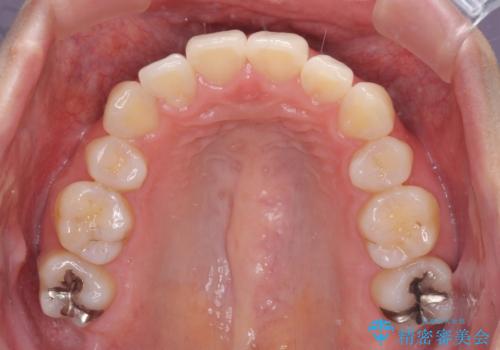

- 抜歯矯正の後戻りで前歯が突出してきていることを気にして来院された患者様です。

口元の突出感を改善するにあたり、抜歯矯正は行うことができないため、奥歯の後方移動とIPR(歯と歯の間を削る)により達成することとしました。

再度後戻りしたときに対応しやすいよう、インビザラインにて矯正治療を行うこととしました。

しっかりと装着時間を守り、ゴムかけにも協力していただいたので、口元を引っ込めることができました。